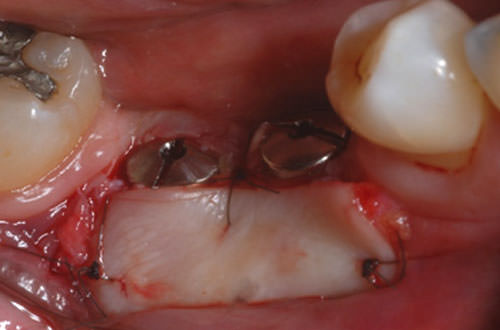

Paciente masculino de 52 años se presentó a la clínica de postgrado en implantología de la Universidad Federal de Santa Catarina (UFSC), con ausencia de los elementos dentales 45 y 46, donde se instalaron 2 implantes. Después del período de oseointegración de los implantes, en la evaluación para la reapertura, se observó que la cantidad de tejido queratinizado era insuficiente en el área a ser rehabilitada (Figura 1). Por lo que se indicó un injerto gingival libre para la obtención de la mucosa queratinizada alrededor de los implantes y profundidad del vestíbulo. Se inicia con una incisión parcial en la línea que divide la mucosa queratinizada de la mucosa alveolar, a partir de esa incisión se comienza a dividir el tejido, manteniendo íntegro el periostio (Figura 2). Se instalaron los cicatrizadores (Figura 3) y se remueve el injerto gingival libre del paladar.

Figura 2

Incisión en la cresta del reborde, con división del colgajo por vestibular.

Figura 3

Cicatrizadores instalados